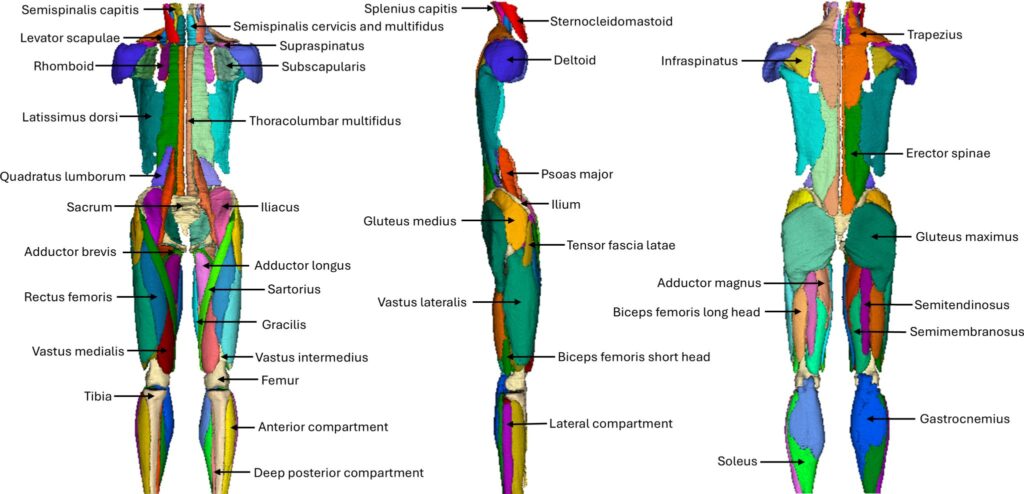

MuscleMap, a productive collaborative co-lead by Weber, Wesselink, McKay and Elliott, is filling this gap. It is an open-source platform for whole-body muscle segmentation and muscle-composition quantification.

MuscleMap draws on data from tens of thousands of scans and analyses using AI, enabling muscle biomarkers to be interpreted relative to population-specific normative ranges.

Recently, MuscleMap has just released an updated v1.2 of the model, trained on an expanded community-sourced dataset, that can automatically quantify 100 muscles and bones.